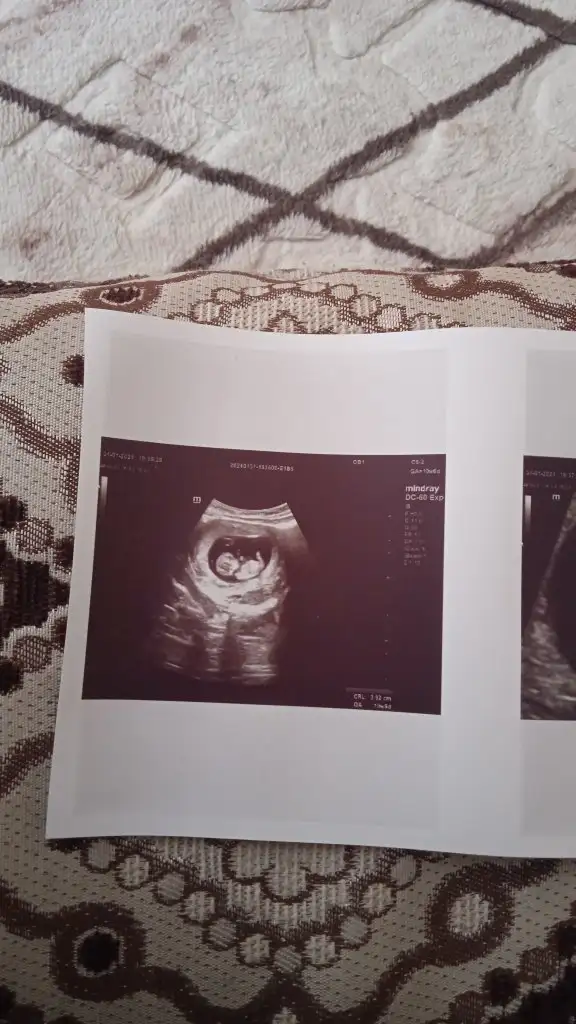

10+1 karından çekildi